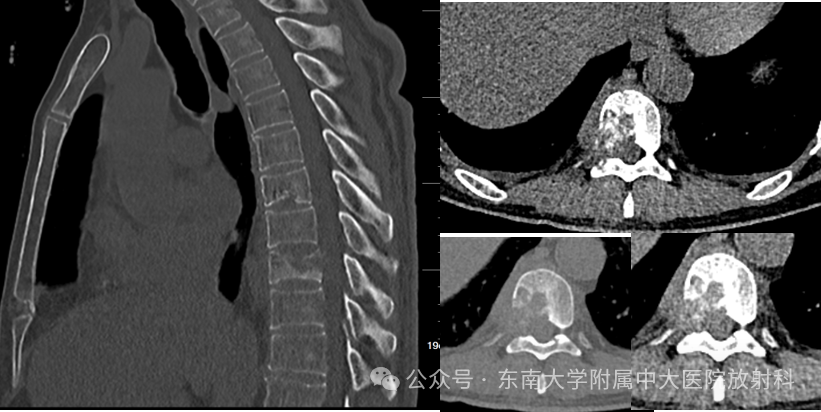

脊柱朗格汉斯细胞组织细胞增生症影像诊断

病例‍ 男,69岁主诉:颈背部疼痛8月余现病史:患者8月前跌倒后感背部疼痛,遂至当地医院就诊,查胸部 X 线显示肋骨骨折,予止双氯芬酸止痛治疗,治疗效果差,一直感背部疼痛明显影像学表现